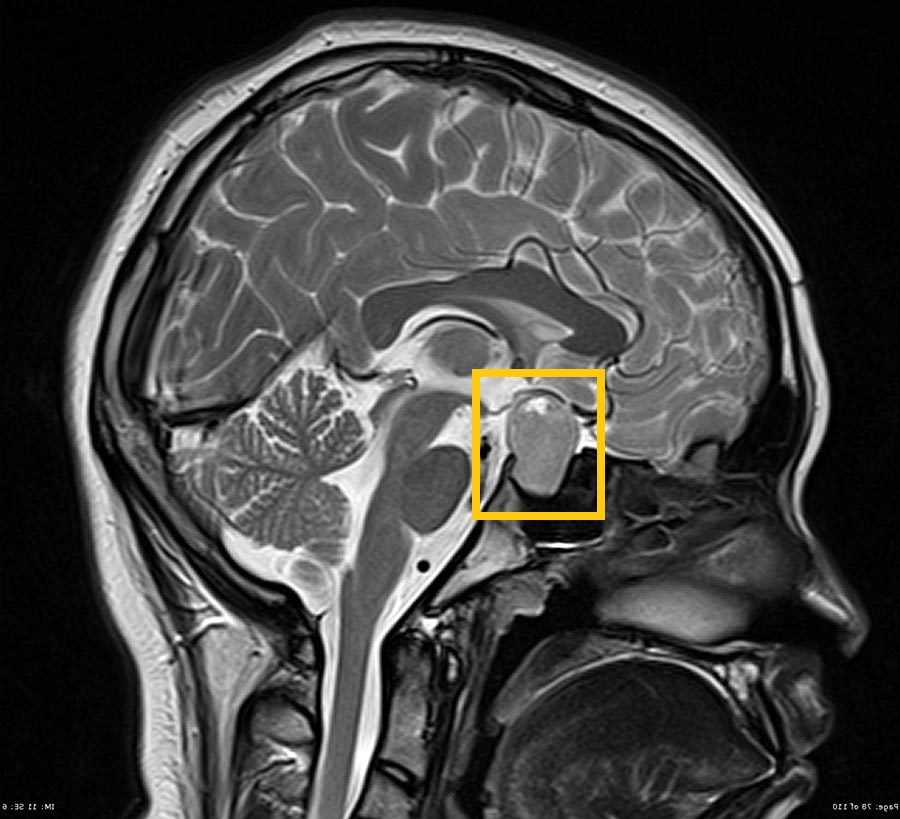

Гипофиз – главный орган эндокринной системы. Он является мозговым придатком и вместе с гипоталамусом образует гипоталамо-гипофизарную систему. Расположен этот орган в так называемом турецком седле. Гипофиз отвечает за выработку гормонов, которые влияют на:

Вес гипофиза 0,5 г. Размеры его могут быть разными. В среднем они составляют в ширину 10-12 мм, в сагиттальной плоскости 8 мм  и 3-8 мм в вертикальной. Размеры гипофиза в норме у женщин могут меняться в зависимости от фазы ментруального цикла. Передне-задний размер в детородном возрасте менее 10 мм, в период менопаузы - менее 8 мм, у девочек до 12 лет - 6 мм и меньше. В период полового созревания у подростков и беременных женщин – 10-12 мм в высоту в сагиттальной плоскости.

Заподозрить патологию гипофиза можно при исследовании головного мозга и затем направить пациента на прицельное МРТ гипофиза с контрастированием. Исследование длится около 60 мин, в результате врач получает снимок гипофиза в 3-х проекциях.

МРТ гипофиза, что показывает?

Наиболее часто встречаемой опухолью гипофиза является аденома – патология, которая харатеризуется разрастанием железистой ткани. Сегодня МР-томография является лучшим методом для ее распознавания и позволяет проводить дифференциальный диагноз среди других новообразований.

Пролактинома является часто встречающейся гормонально активной опухолью. Его повышение в плазме крови выше 100-150 нг/мл является патогномоничным симптомом пролактимомы. Гиперсекреция пролактина может приводить к различным заболевания, таким как бесплодие, аменорея и др. Повышение пролактина не является обязательным признаком опухоли гипофиза. Его значение может увеличиваться при наличии других опухолей, а также при приеме некоторых лекарственных препаратов. МРТ гипофиза при повышенном пролактине целесообразно проводить для диагностики причины его отклонения от нормы, выявлении опухоли, определении ее размеров, динамики роста, отношения к другим окружающим структурам, наличии дополнительных структур в самой опухоли.

Гормонально активные опухоли провоцируют развитие типичных эндокринопатий (акромегалия, синдром Кушинга), в связи с чем их можно диагностировать на ранних этапах. Как правило, такие опухоли на момент выявления имеют небольшие размеры (микроаденомы, т.е. опухоли до 10 мм). Гормонально неактивные опухоли проявляют себя, сдавливая окружающие структуры. После введения контрастного вещества микроаденомы, как правило, выглядят гипоинтенсивными по сравнению с нормальной тканью гипофиза, интенсивно накапливающей контрастный препарат. Макроаденомы (опухоли больше 10 мм), напротив, быстро аккумулирует контрастное вещество, выделяясь на фоне окружающих структур.

Результаты исследований показывают, что применение МР-томографии с контрастным усилением для диагностики патологии гипофиза помогает поставить точный диагноз и помогает врачу подобрать необходимую тактику лечения.